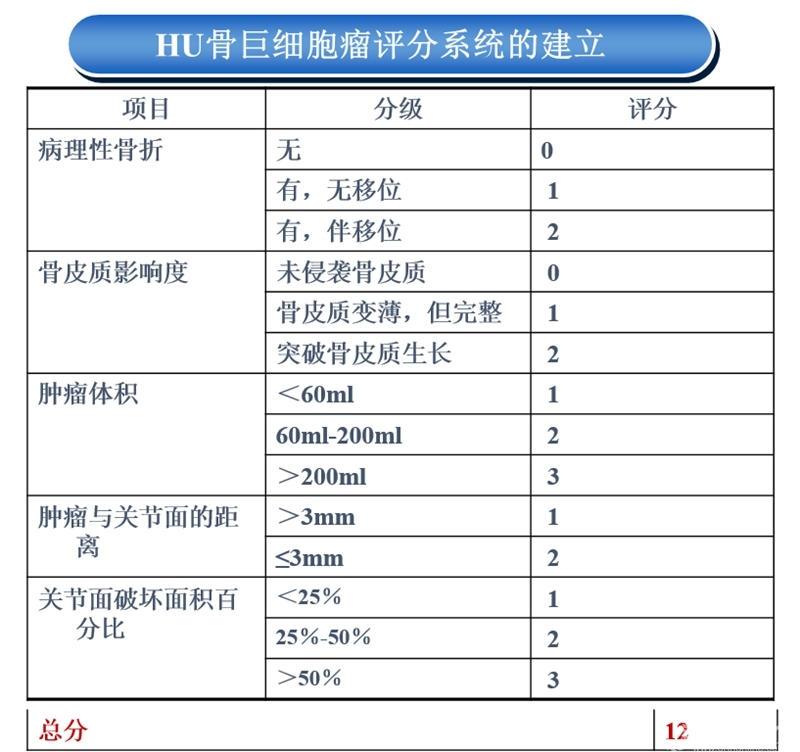

随即他联络国内12家各省级最大骨肿瘤治疗中心,于2009年成立中国骨巨细胞瘤协作组(GTOC),简称为“GTOC学组”。协作组通过成立课题研究小组、专家遴选进而初拟了指标体系的准备工作,又经过2轮的专家咨询、统计处理,进而完成Hu GCTS的构建。

在高水平循证医学证据缺失情况下,权威专家的共识观点是循证医学的关键所在。根据GTOC多中心流行病学数据统计,肿瘤关节假体置换手术占到股骨远端GCT病例总数的1/3(99例/302例)左右,学组专家纷纷表示此类患者的诊治需引起重视,在大家的共同努力下HU骨巨细胞瘤评分系统的建立,用于指导骨肿瘤科医生制定手术策略。

HU骨巨细胞瘤评分系统

手术策略的制定